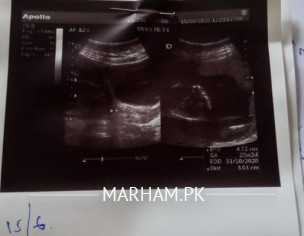

She has pregnancy of 5 months and has lower abdominal pain and heaviness so please elaborate the attached ultrasound report and need gynecologist opinion. Dr. Is saying the uterus length is getting smaller and stitches are required in future. Is it true according to ultrasound attached.

In previous usg, the cervical length was 4.8 cm while in the latest one it became 3.5 cm.

ok-she needs a prophylactic circlage tht can b given before 12 wks-so instead of landing in emergency do it elective-ethg success lies wth Almighty-v can only make efforts